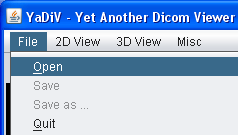

To open a series of DICOM files, select "File → Open" from the main menu. In the upcomming dialog, open the directory containing the DICOM files and select a single file. YaDiV will automatically open all files in the same directory belonging to the series of the selected file. Series with files stored in more than one directoriy are (currently!) not supported. While the series is loading, you can already browse through the DICOM files which have been loaded so far using the Image Selector.